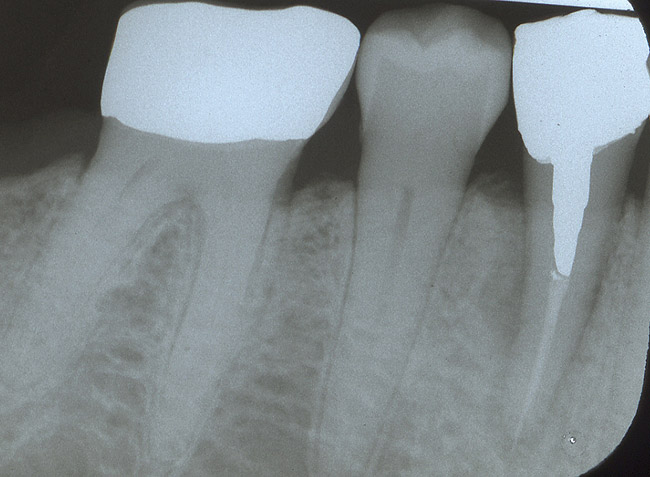

The patient was a 55-year-old woman referred for evaluation of tooth No. 30 (Figure 3A). The tooth presented with a fractured root and was deemed nonrestorable. After a full thickness flap elevation, tooth No. 30 was extracted using an elevator and forceps. It was decided to preserve the socket because the site was planned to have an implant-supported restoration. The socket was grafted using freeze-dried bone allograft mixed with CAPSET (calcium sulfate bone graft barrier).a The socket was allowed to heal for 4 months (Figure 3B). After the healing period, the patient was scheduled to have an implant placed (Figure 3C). At the time of placement, it was noted that the bone appeared to be dense and firm to the touch. The implant was placed uneventfully (Figure 3D) and was successfully restored after a 3-month healing period. The patient has been followed for over 3 years and is functioning well using the implant-supported restoration.

Figure 3a  Tooth No. 30 presented with a fractured root deemed nonrestorable.

Figure 3a

Figure 3c  After the healing period, the patient had an implant placed.

Figure 3c